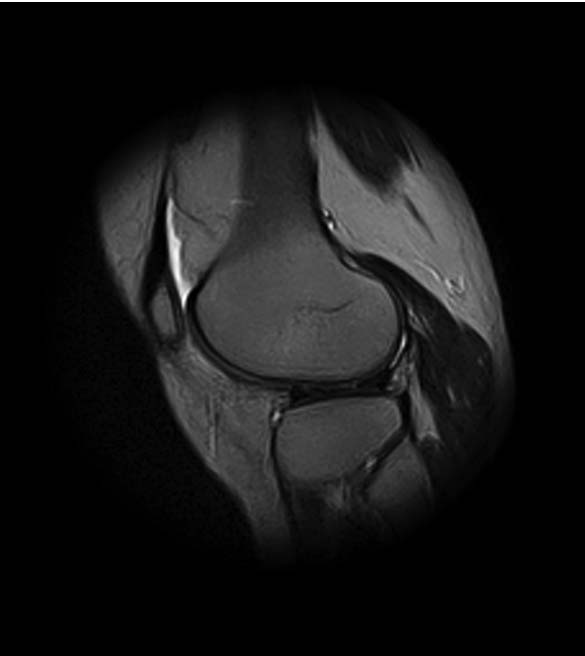

добрый день! Не очень понятен принцип, по которому отбирались снимки МРТ. Большинство из них не показательны. Вижу пока только повреждение хряща на феморопателлярной поверхности. Хлтелось бы посмотреть диск целиком

На снимках повреждений наружного мениска не вижу и кисты мениска не вижу. Есть повреждение хряща на передней поверхности внутреннего мыщелка бедра. Вполне может оказаться, что повреждение лоскутное. А какая консервативная терапия проводилась?